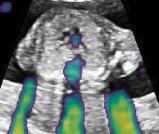

Fig. 6 compares the shadow confidence maps of the state-of-the-art methods and the proposed methods. RW and have the same parameters as used for Table I. The shadow confidence maps of the baseline, the proposed method and the proposedAG method are generated directly from input shadow images by confidence estimation networks. Overall, the proposed method and the proposedAG method achieve more visually reasonable shadow confidence estimation than the baseline and the state-of-the-art on different anatomical structures shown in Fig. 6. The proposed method and the proposedAG method are able to highlight multiple shadow regions while the RW algorithm shows limitations for most cases, especially for disjoint shadow regions.

Row I in Fig. 6 shows a fetal brain image from . The confidence estimation of shadow regions from the baseline, the proposed method and the proposedAG method are similarly accurate since we use fetal brain images to train the confidence estimation networks in these three methods. These outperform [16] and [22]. Rows (II-IV) in Fig. 6 show shadow confidence maps of non-brain anatomy from , including lips, abdominal and cardiac. The baseline failed on unseen data during inference. However, the proposed methods are able to generate accurate shadow confidence maps because of the generalized shadow features obtained by the shadow-seg module. Furthermore, the “Lips” example shows that our method is capable of detecting weaker shadow regions that have not been annotated in manual segmentation. This indicates that the confidence estimation network has learned general properties of shadow regions.